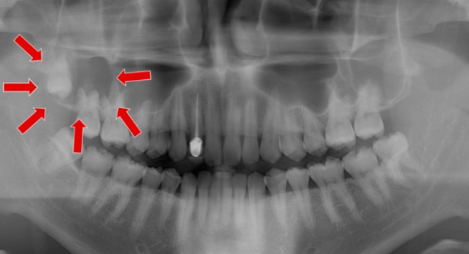

복잡 매복 발치 :27,900 ~ 29,200원 (2022년 일반 의원급 기준)

잇몸이 덮여져 있는 상태로 치아를 분리 발 거할 경우입니다.

완전 매복 발치 : 36,600 ~ 37,900원 (2022년 일반 의원급 기준)

치아머리 부분이 치조골에 2/3 이상 매복된 상태로 치조골 삭제 및 치아 분할 술을 같이했을 경우입니다.